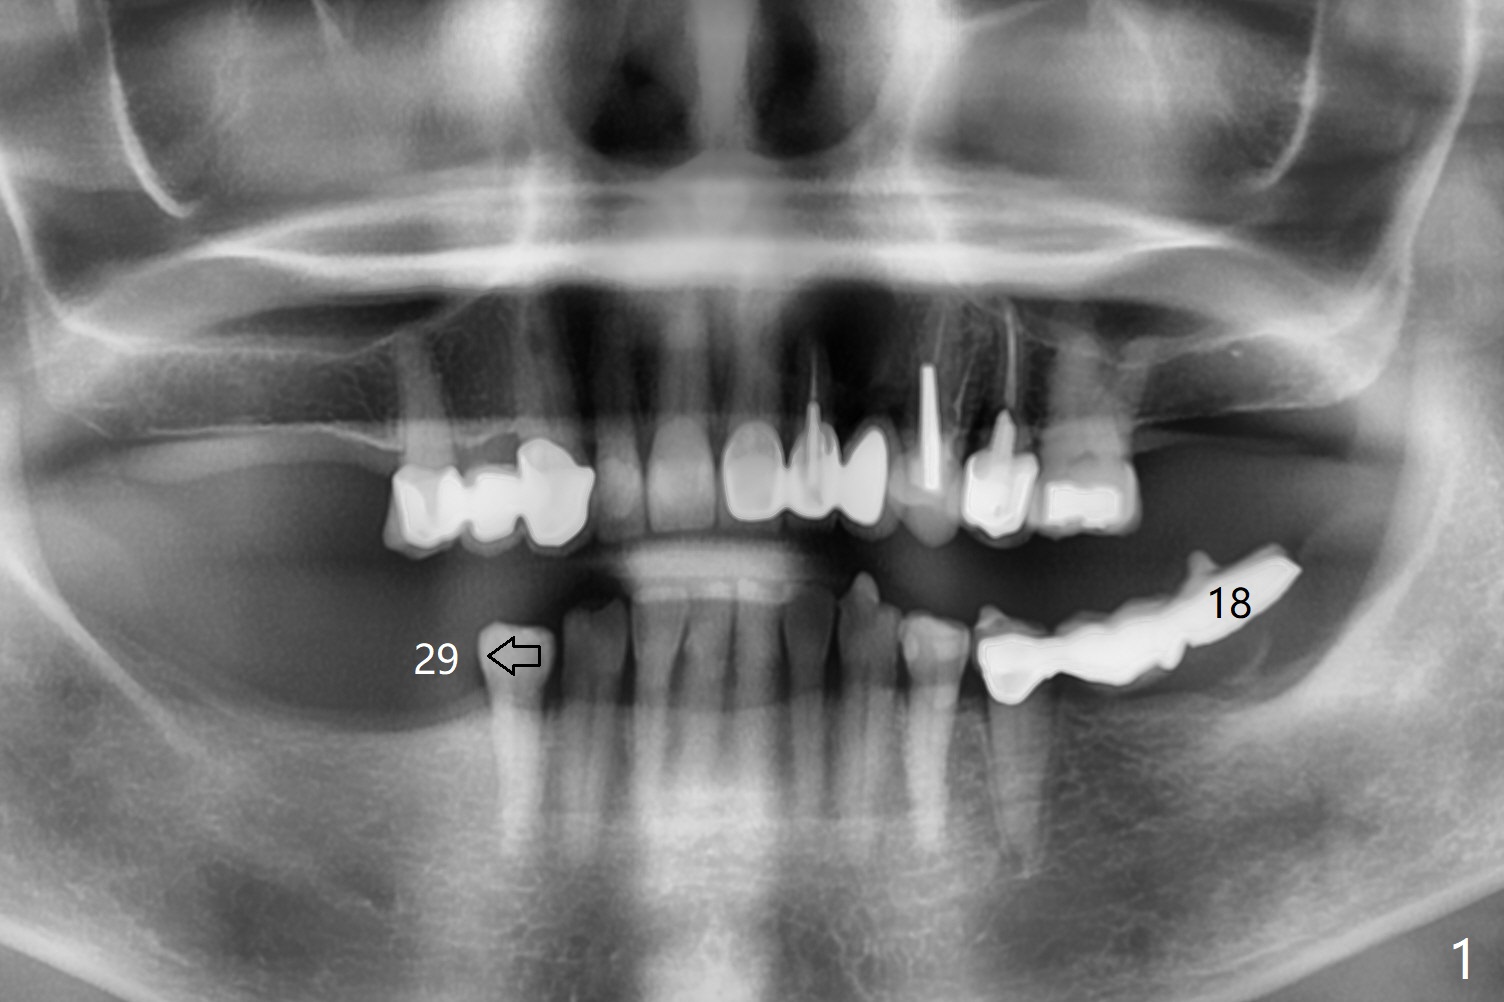

Profile Drill

A 73-year-old woman has interest in implants at #19 and 29 (Fig.1). The ridge is not even, higher mesio(*)lingually (L, Fig.2,3). After implant placement, use profile drill (5.5 or 6.0 mm) to facilitate healing abutment placement.